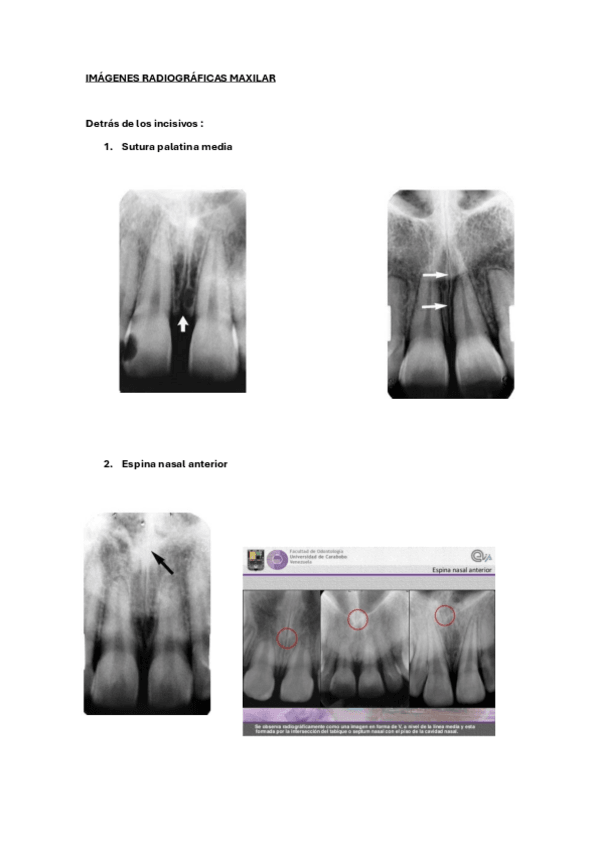

IMÁGENER RADIOGRÁFICAS MANDÍBULA

He publicado nuevos apuntes de 2º Radiología bucal: IMÁGENER RADIOGRÁFICAS MANDÍBULA

IMAGENER-RADIOGRAFICAS-MANDIBULA.pdf

IMAGENES-RADIOGRAFICAS-MAXILAR.pdf